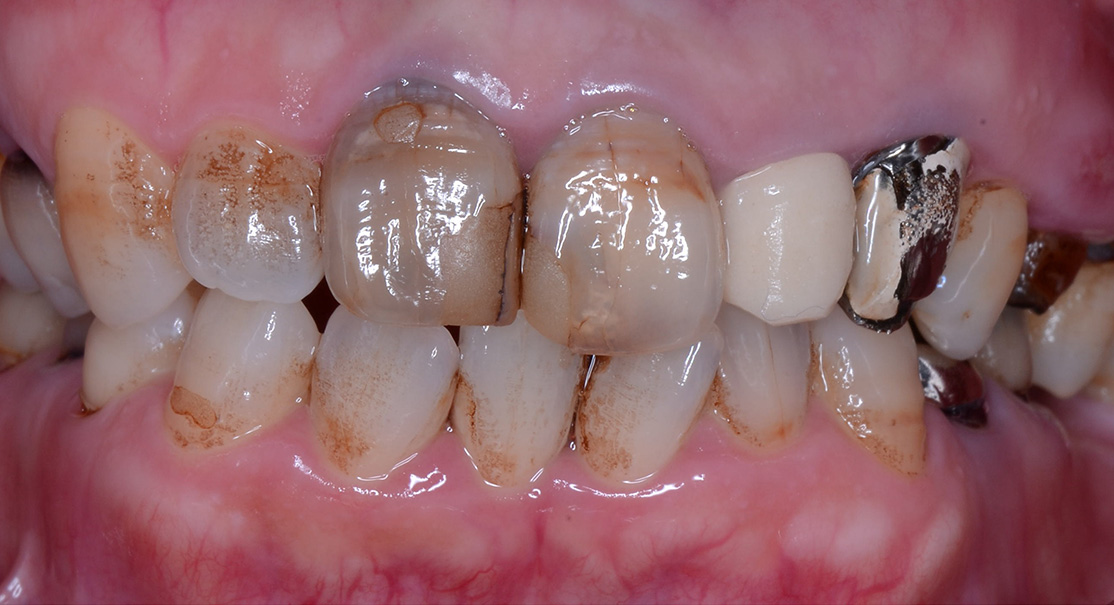

主訴 前歯が折れた 全体的に診てほしい

問題点

・20年以上歯科医院に行かず虫歯を放置していた。

・歯科治療に対し恐怖心があった。

治療計画

・虫歯を長期間放置していたため、審美障害、咬合平面の崩壊、顎位の偏位、臼歯の舌側傾斜、歯周病の罹患等々様々な問題が生じていました。

・患者様にはまず虫歯の治療、歯周病の治療を行い、最終的にクラウン等で歯冠修復が必要という説明をさせて頂きました。

主訴 前歯が折れた

全体的に診てほしい